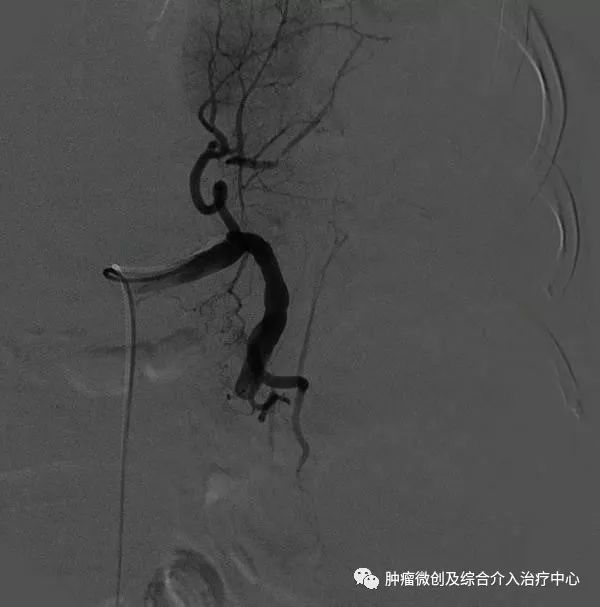

3.根据脾脏病变及不同的栓塞方法选择栓塞材料。部分脾动脉栓塞多采用明胶海绵颗粒,约2mm3,浸入含青霉素和庆大霉霉素的生理盐水中;也有主张用明胶海绵短条,约2mm×8mm大小,插入2ml注射器乳头中注入,一般为6~8条。栓塞时导管尽量超选至深处,最好越过胰背动脉,以防误栓造成医源性胰腺炎。术中通常根据脾动脉的血流来判断脾脏栓塞程度,笔者的经验是脾动脉血流稍减慢栓塞范围为30%~40%,明显减慢为50%~60%,若短暂停流后呈蠕动前进为70%~80%。全脾栓塞时多采用明胶海绵粉末或无水乙醇,导管超选应更为准确、深入,必要时可通过3F微导管或球囊导管注入无水乙醇等液态栓塞剂,以免反流。脾动脉主干栓塞时多选用不锈钢螺圈,栓子直径应略大于脾动脉管径,导管置于脾动脉近端,但仍应越过胰背动脉开口。

4.再次脾动脉造影,明确脾栓塞程度。若感不足,可补加栓塞,直至满意为止。退出导管,穿刺处压迫止血后加压包扎,平卧24h。